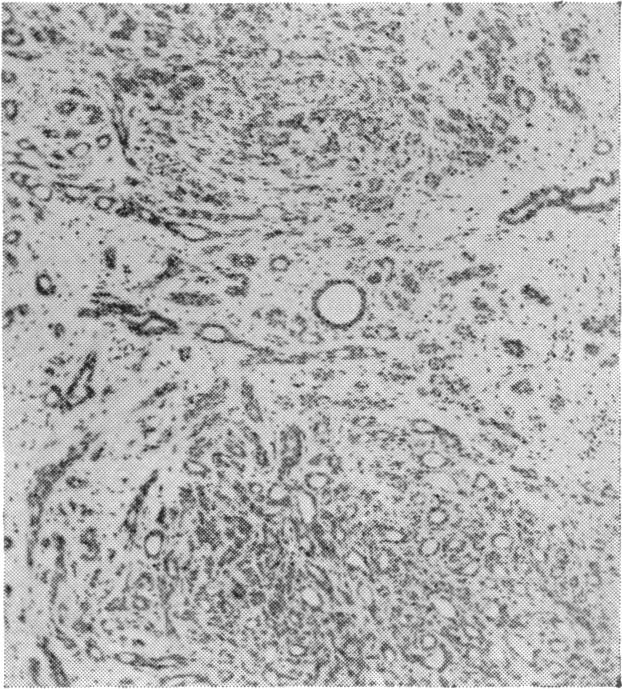

Carcinoma of the breast: a review of the treatment.

Ann R Coll Surg Engl. 1954 Apr;14(4):215-46.